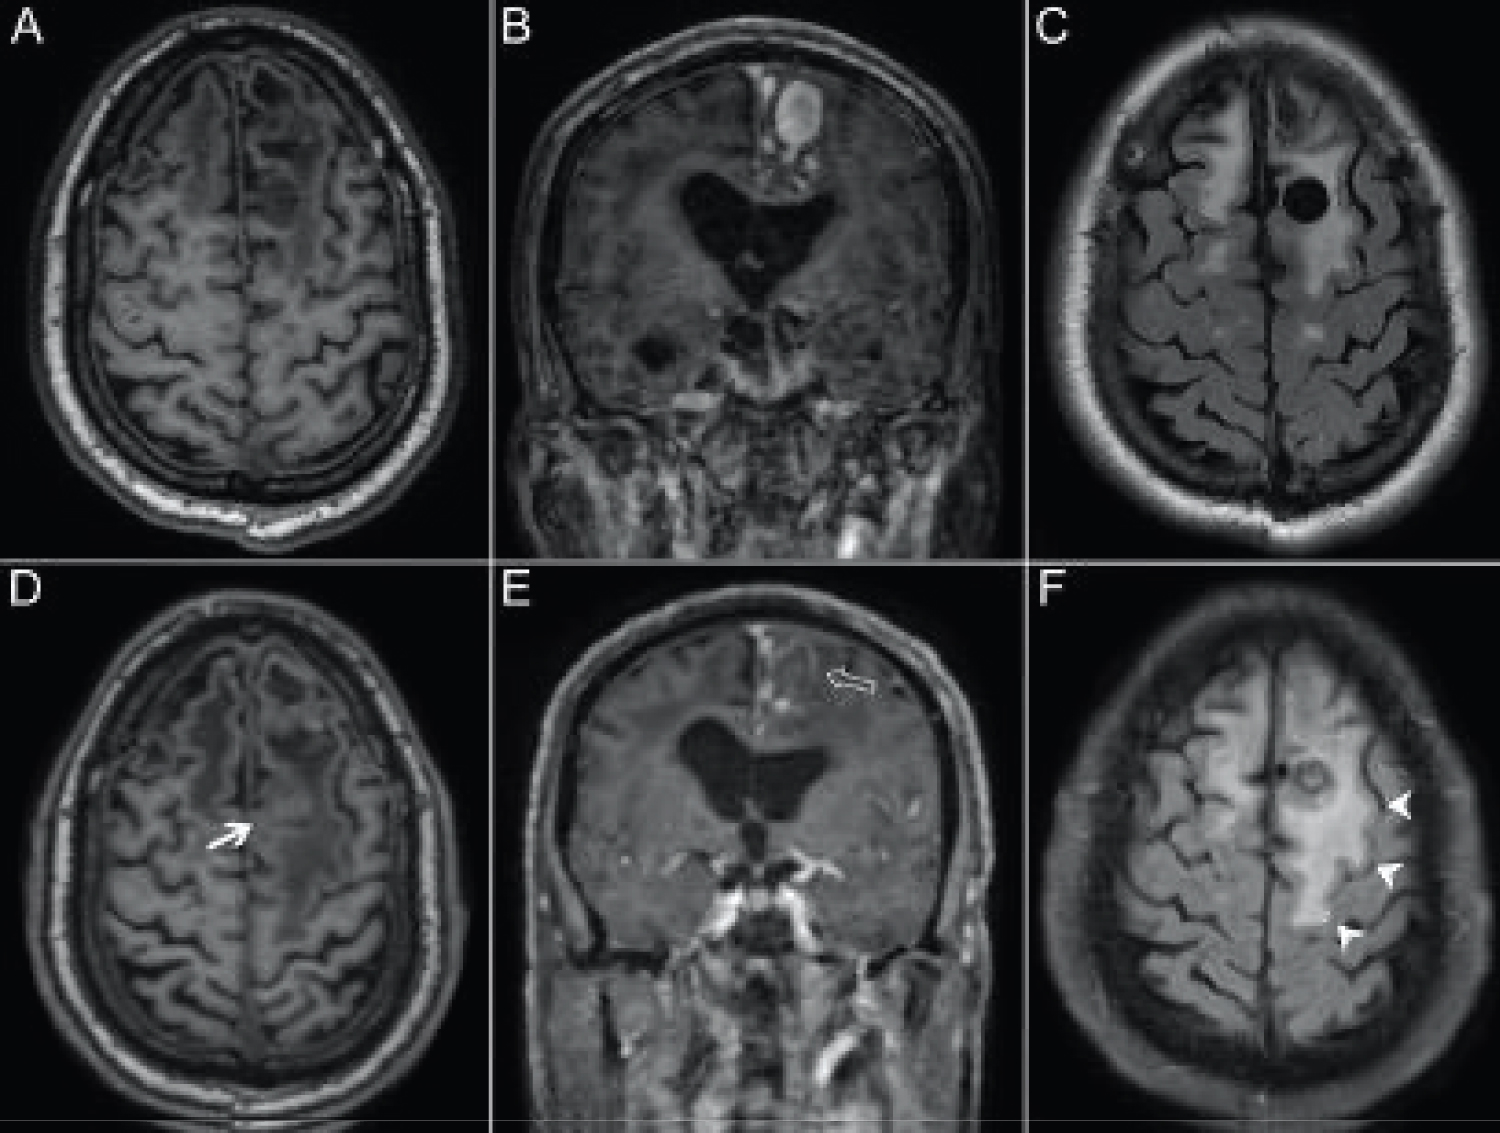

The patient's left frontal lobe AVM was first identified in 2007 with a nidus measuring approximately 21 × 20 × 21 mm. Arterial supply was predominantly from small arterial branches arising the pericallosal and callosomarginal branches of the left anterior cerebral artery. A large tortuous vein provided superficial drainage into the superior sagittal sinus. On follow up imaging, computed tomography angiography (CTA) demonstrated an interval decrease in contrast enhancement within the venous varix (Figure 1). Magnetic resonance imaging (MRI) findings were also suggestive of partial thrombosis within this venous varix and demonstrated an interval increase in vasogenic perivenous edema within the left superior frontal lobe (Figure 2). Four months later the patient underwent digital subtraction angiography (DSA), which revealed a significant decrease in nidus size, suggesting partial thrombosis of the nidus in addition to draining vein thrombosis (Figure 3). Notably, the large ectatic cortical vein draining the residual nidus was now seen to empty into multiple convexity cortical veins, whereas it had previously drained predominantly into the superior sagittal sinus, again suggestive of interval thrombosis of the draining vein.

Figure 1: CT Angiogram in November of 2017 (Sagittal [A], coronal [B]) and in October of 2020 (Sagittal [A], coronal [B]). The draining vein of the left frontal AVM is associated with a large saccular venous aneurysm. In C and D, there is an interval decrease in contrast filling of the venous aneurysm. View Figure 1

Figure 2: Axial T1 without gadolinium (A), Coronal T1 with gadolinium (B) and axial T2 of the brain undertaken in 2017 followed with axial T1 without gadolinium (D), coronal T1 with gadolinium (E) and axial T2 of the brain undertaken in October of 2020. (A & D) Axial T1-weighted MRI imaging demonstrating an interval decrease in signal void within the draining vein aneurysm (bold arrow), suggesting partial thrombosis; (B & E) Coronal T1-weighted MRI-imaging post-contrast demonstrating an interval loss of contrast enhancement within the venous aneurysm (arrow outline); (C & F) Axial T2-FLAIR MRI demonstrating an interval increase in perivenous edema throughout the left superior frontal lobe (arrowheads). View Figure 2